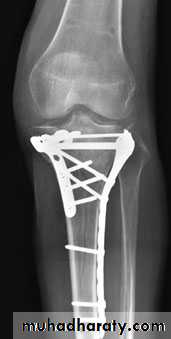

For displaced fractures

Lower limb

treatment is by open reduction and internal fixation with

plate and screws as it is an intra articular fracture.

fixation of tibial plateau fracture